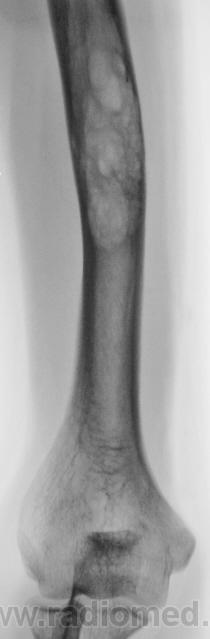

Предположу - хондрома. В пятницу наблюдал такую же картинку. Правда было булавовидное расширение, а в остальном также.

фиброзная дисплазия

Больше за фиброзную остеодисплазию.

+1 за фиброзную дисплазию.

А, как похоже на адамантиному...

не похоже - ни локализация, ни рентгеновская картина - нет интракортикальных очагов

Похоже, эти 2 процесса обычно и дифференцируют друг с другом. Но для фиброзной остеодисплазии характерно саблевидное искривление кости, а для адамантиномы - не очень

Был уверен, что представленные мною снимки взяты с нашего сайта! Они у меня в архиве как фиброзная дисплазия.Честно говоря отдифференцировать эти две нозологии это высший пилотаж.